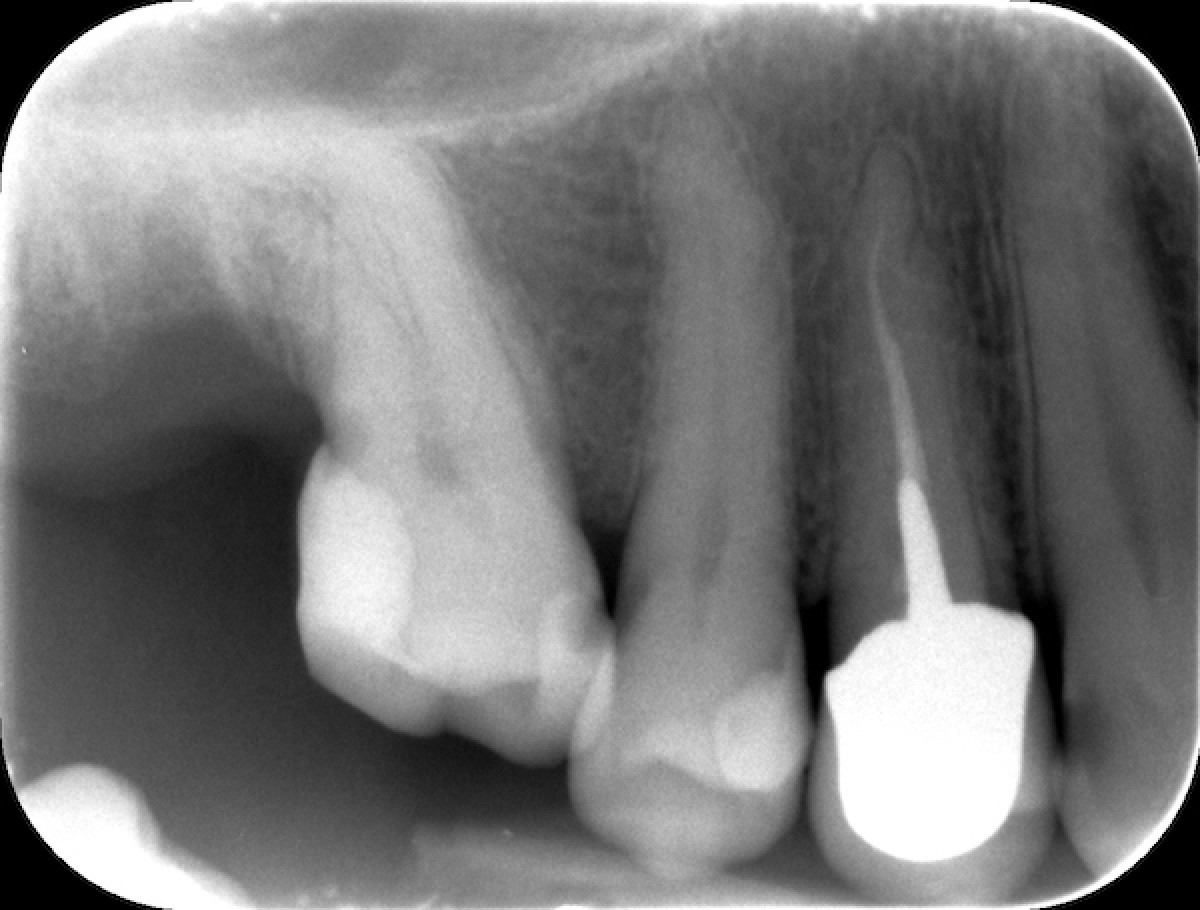

Heat treated Niti Alloys and modern Endodontics Dentistry33

From www.dentistry33.com

Heat treated Niti Alloys and modern Endodontics Dentistry33 Ni Ti Alloy In Dentistry This review aims to provide an overview of nitinol alloys used in dentistry in order for its unique characteristics to be appreciated. Compared the tribological resistance of niti alloy to pure ti and ni and found it to be, respectively, 30 times (ti) and 10 times (ni). In modern orthodontics, the choice of materials plays a significant role in achieving. Ni Ti Alloy In Dentistry.

Heat treated Niti Alloys and modern Endodontics Dentistry33 Ni Ti Alloy In Dentistry An overview of niti shape memory alloy: Firstly, the niti applications in dentistry like orthodontic wires as well as endodontic fields are presented. Compared the tribological resistance of niti alloy to pure ti and ni and found it to be, respectively, 30 times (ti) and 10 times (ni). Corrosion resistance and antibacterial inhibition for dental application. This review aims to. Ni Ti Alloy In Dentistry.

Heat treated Niti Alloys and modern Endodontics Dentistry33 Ni Ti Alloy In Dentistry An overview of niti shape memory alloy: Compared the tribological resistance of niti alloy to pure ti and ni and found it to be, respectively, 30 times (ti) and 10 times (ni). In modern orthodontics, the choice of materials plays a significant role in achieving optimal outcomes. This review aims to provide an overview of nitinol alloys used in dentistry. Ni Ti Alloy In Dentistry.

Heat treated Niti Alloys and modern Endodontics Dentistry33 Ni Ti Alloy In Dentistry Compared the tribological resistance of niti alloy to pure ti and ni and found it to be, respectively, 30 times (ti) and 10 times (ni). An overview of niti shape memory alloy: Firstly, the niti applications in dentistry like orthodontic wires as well as endodontic fields are presented. Corrosion resistance and antibacterial inhibition for dental application. In modern orthodontics, the. Ni Ti Alloy In Dentistry.